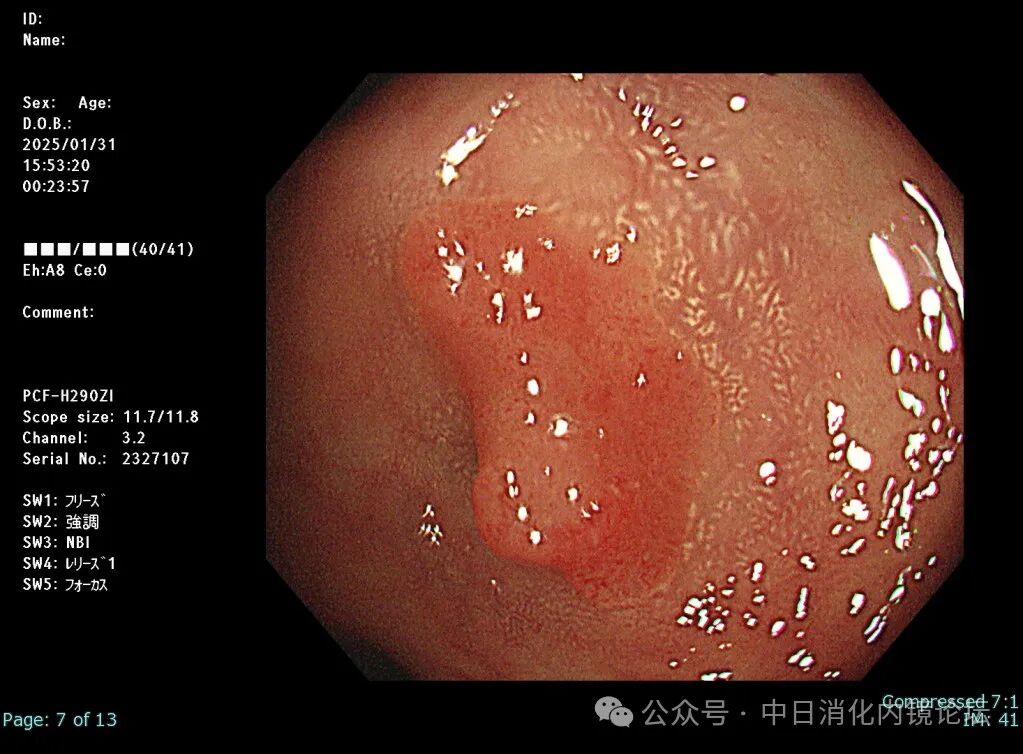

在繁忙的临床工作中按照日本消化内镜学会倡导的病变观察流程,便可事半功倍,极大地提高诊断准确性和检查效率。病变观察远景→近景→放大,白光→NBIJNET→靛胭脂 pit pattern。切除后创面确认,确保无残留,断端阴性→肛侧腹侧点墨标记→标本固定,为病理诊断以及今后可能的追加治疗提供完整精确的原始资料。